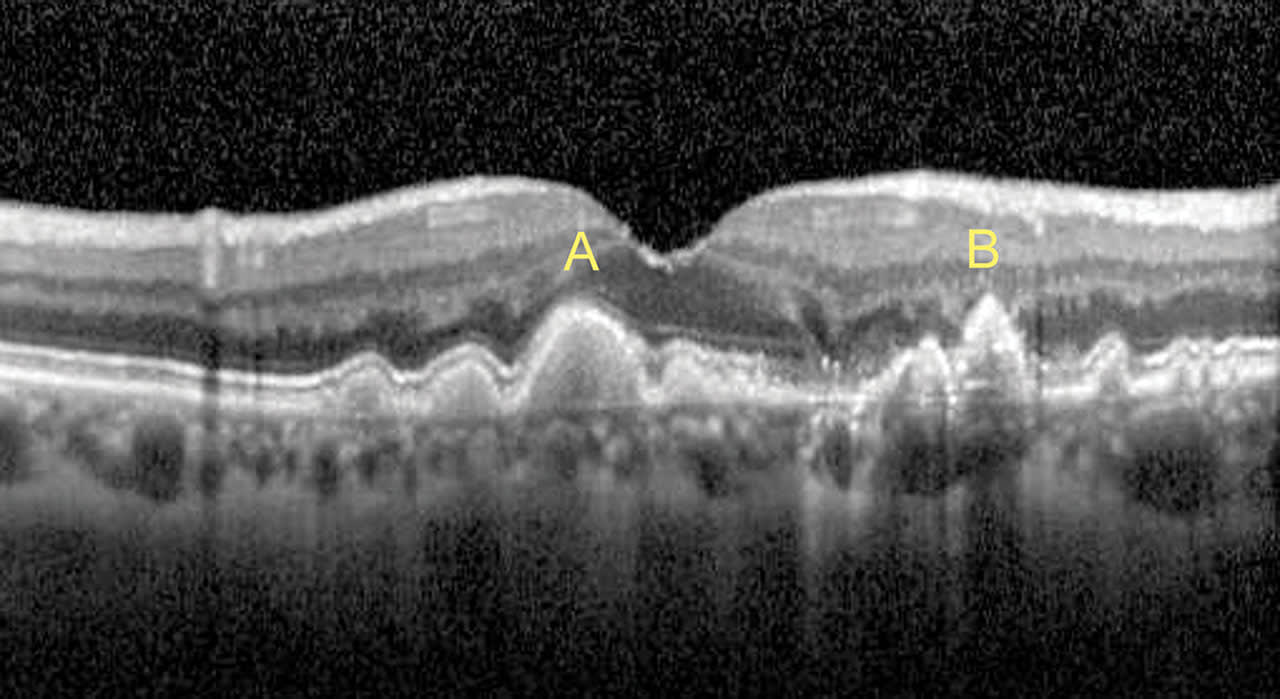

Another common use of diagnostic OCT is to evaluate drusen, which are aging deposits of lipids and proteins under the retina.2 The different types of drusen are evident on OCT B-scans: soft drusen, hard drusen and reticular pseudodrusen.

Soft drusen develop under the RPE and have a round, dome appearance. (Figure 8a). Hard drusen are also sub-RPE but have a conical or peaked appearance (Figure 8b). Reticular pseudodrusen are present above the RPE (Figure 9) and can provide further prognostic value, as patients with RPD have a significant risk for the progression of age-related macular degeneration (AMD).3